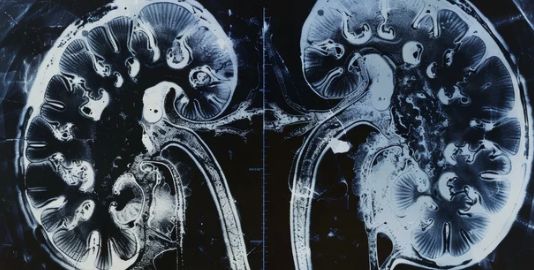

3) 영상 검사

- 초음파 또는 CT 스캔으로 신장 크기와 구조 확인.